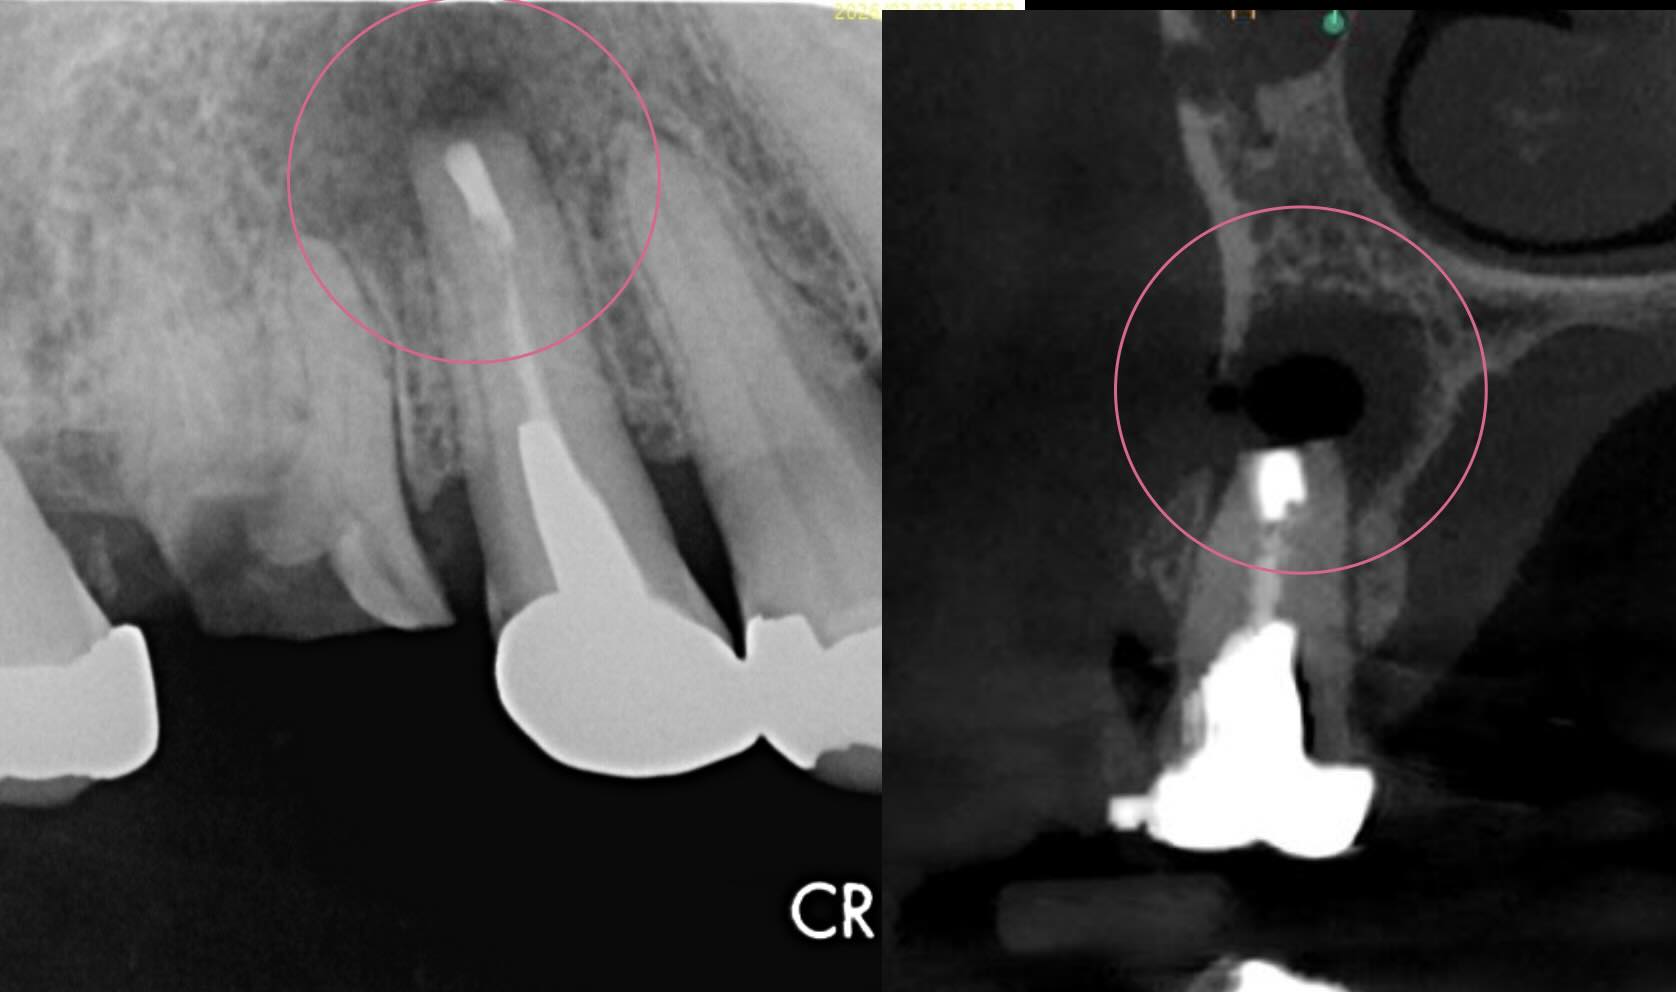

治療後

| 診断名 | pulp diagnosis : Previously treated periapical diagnosis : Acute apical abscess |

| 治療の方法 | 歯根端切除術(右上5番) |

現時点で経過は良好で、この歯は保存できる可能性が高い状態です。

また経過を報告します!